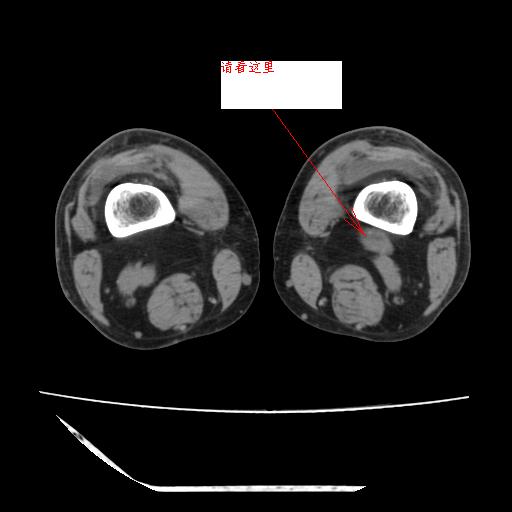

这是由于两侧的肌肉不对称所致,加上扫描的平面也有些差异。请看示意图:

这个病例诊断:退行性骨关节炎